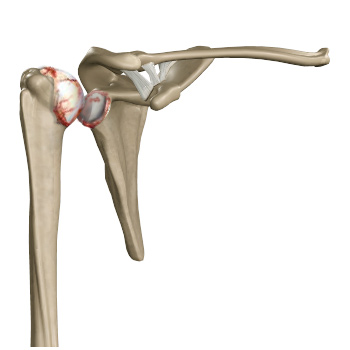

The term arthritis literally means inflammation of a joint but is generally used to describe any condition in which there is damage to the cartilage. Damage of the cartilage in the shoulder joint causes shoulder arthritis. Inflammation is the body's natural response to injury. The warning signs that inflammation presents are redness, swelling, heat, and pain.

The cartilage is padding that absorbs stress. The proportion of cartilage damage and synovial inflammation varies with the type and stage of arthritis. Usually, the initial pain is due to inflammation. In the later stages, when the cartilage is worn away, most of the pain comes from the mechanical friction of raw bones rubbing on each other.

With osteoarthritis, the cartilage starts to wear away over time. In extreme cases, the cartilage can completely wear away, leaving nothing to protect the bones in a joint, causing bone-on-bone contact. Bones may also bulge or stick out at the end of a joint and are called bone spurs.

- The cartilage lining is thinner than normal or completely absent. The degree of cartilage damage and inflammation varies with the type and stage of arthritis.

- The capsule of the arthritic shoulder is swollen.

- Bone spurs or excessive bone can also build up around the edges of the joint.